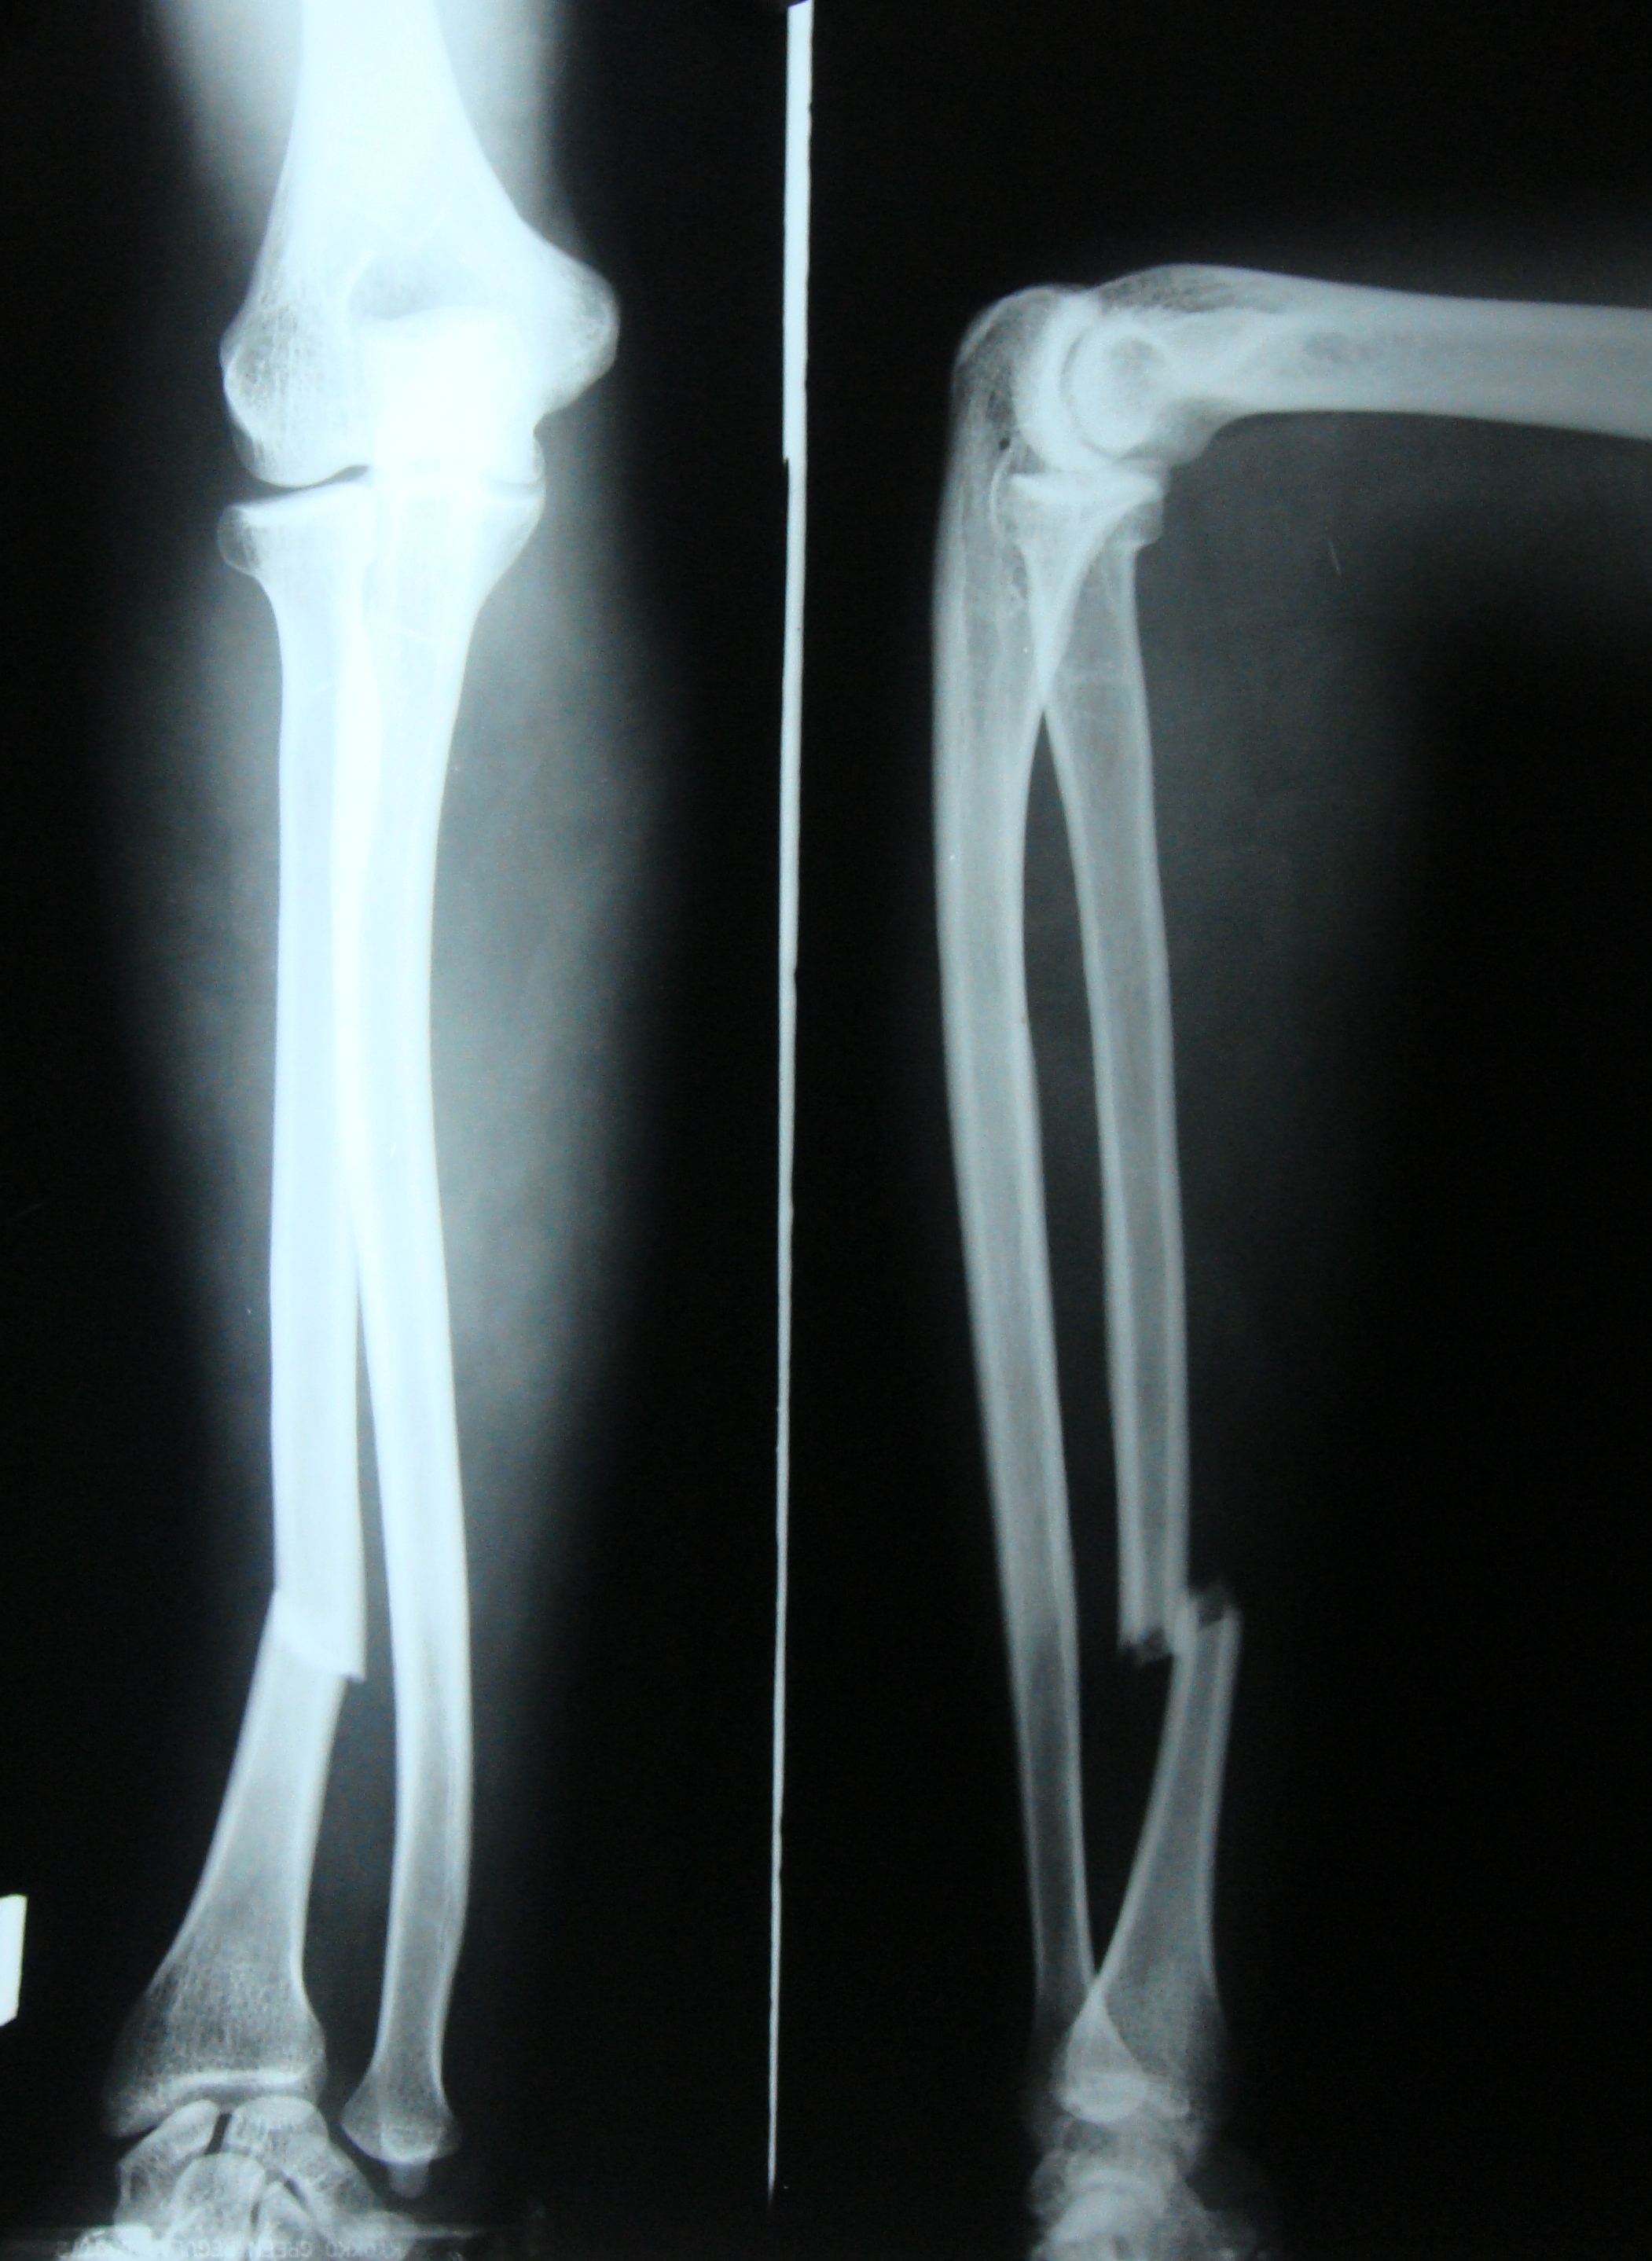

Fractures range from small partial cracks to complete breaks and can occur in any bone.

fracture In more severe cases, the bone may be broken into several fragments, known as a comminuted fracture. Overuse or repetitive motions can cause stress fractures. Fracture d�une porte, d�une serrure. Extends all the way across the bone (most common) transverse fracture: A fracture is a break in the continuity of a bone. An attorney intending on climbing the career ladder toward success finds an unlikely opponent in a manipulative criminal he. Rita riportò due fratture nell�incidente. Fractures usually fall within a set number of patterns.

comminuted fracture Ortho/PT Pinterest Radiology, Rad tech and

orthopedics How to tell if my leg fracture is healing? Health Stack